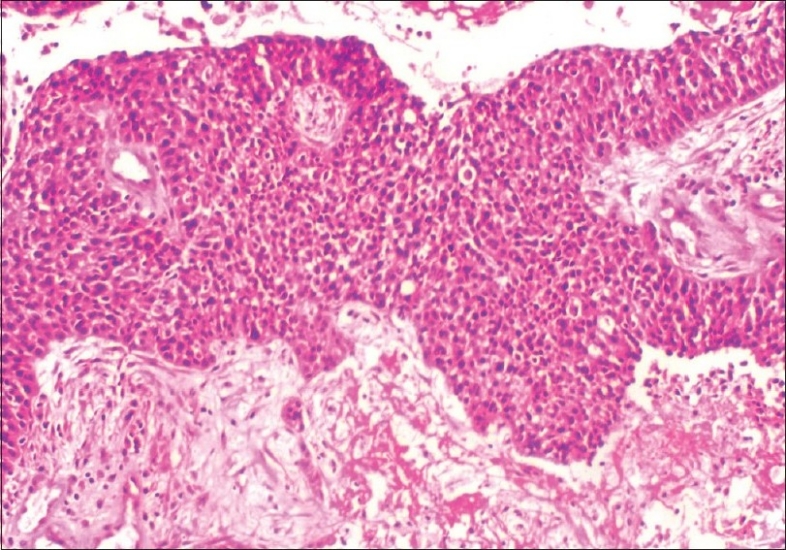

Intraoperative frozen section from the tumor was reported as malignant epithelial tumor. In view of this, a total abdominal hysterectomy, bilateral salpingo-oophorectomy, infra-colic omentectomy, appendicectomy, bilateral pelvic and para-aortic lymphadenectomy, along with multiple peritoneal biopsies, were performed. Final histopathologic examination showed transitional cell carcinoma of the left fallopian tube with marked desmoplastic reaction, papillary fronds and areas of necrosis and invasion of the muscular wall[Figures wall[Figures33 and and4].4]. Both ovaries and uterus were free of disease. Retroperitoneal nodes, omentum and appendix showed no evidence of metastasis. Ascitic fluid cytology was negative for malignant cells. Hence a final diagnosis of transitional cell carcinoma of left fallopian tube, FIGO stage IC, was made.

| Figure 3 Microscopy - neoplastic cells in sheets and trabeculae. Necrotic cells can also be seen, H and E, ×100

| Figure 4 Microscopy-cells arranged around a central vascular core. Many mitotic figures are also seen, H and E, ×200